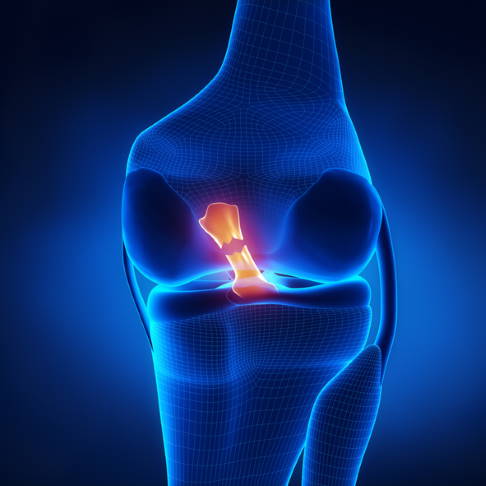

- Instabilität des Kniegelenks z. B. nach Außenbandverletzungen und Kreuzbandriss

- komplexe Verletzungen des Kniegelenks mit Beteiligung von Kreuzband und Innenmeniskus und osteochondralen Läsionen (Knochen-Knorpelschäden)

Meniskusriss und Meniskusverschleiß

Eine häufige Ursache für Gonarthrose ist eine Schädigung der Menisken. Sind sie beschädigt, üben sie ihre mechanische Pufferfunktion nicht mehr ausreichend aus. Diese Meniskusdegeneration beschleunigt sich mit zunehmender Kniearthrose. Auch eine Instabilität des Knies nach einem Kreuzbandriss erhöht den Meniskusverschleiß. Meniskusrisse können z. B. durch Bildung scharfer Kanten den Knorpelabrieb erhöhen. Der Verlust der Meniskusfunktion (Stoßdämpfung) verstärkt den Arthroseprozess.

Bandschäden am Knie

Kniearthrose greift die Seitenbänder und die Kreuzbänder des Kniegelenks ebenfalls an. Die Bänder können das Knie immer weniger stabilisieren, was den Krankheitsprozess wiederum beschleunigt. Lockere oder geschädigte Kreuzbänder sind ein häufiger Auslöser von Gelenkverschleiß im Knie. Ober- und Unterschenkel sind dann nicht mehr stabil miteinander verbunden. Diese Überbeweglichkeit begünstigt den Knorpelabbau an den Gelenkflächen.